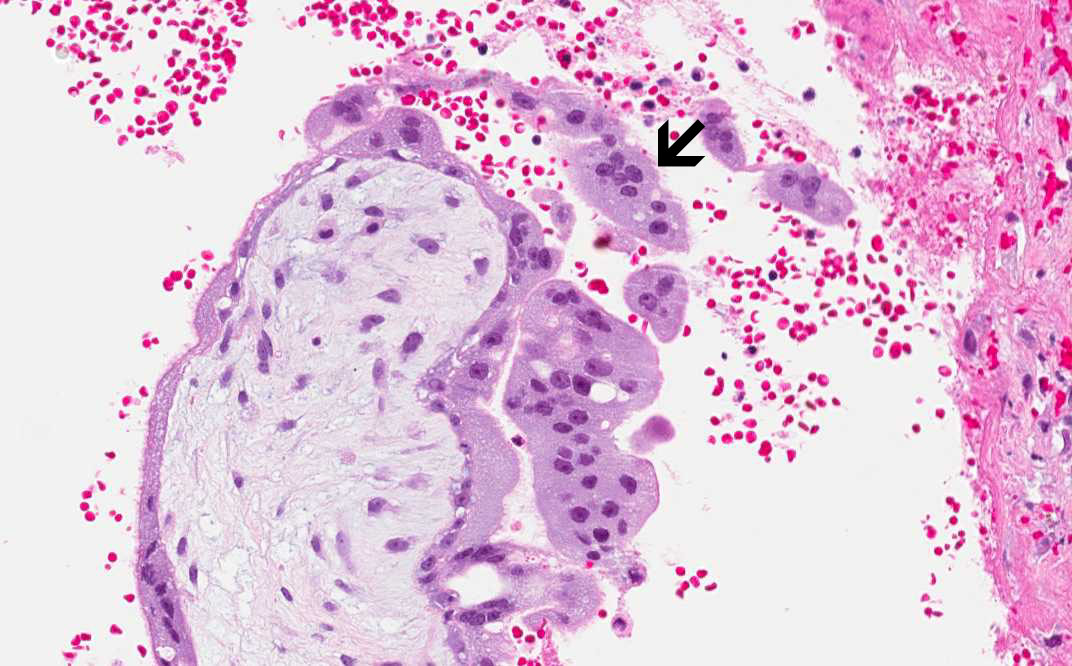

• Trophoblastic villi are noted in Area 1 but no fetal tissue is noted. Trophoblastic villi are far more common to be found than fetal tissues in these cases. Note the multinucleated syncytiotrophoblasts (arrow).

Area 1: The trophoblastic villi are illustrated here. Note the syncytiotrophoblasts (arrow).

Area 3: Compare the structure of the trophoblastic villi with the villi of the normal fallopian tube being illustrated here.